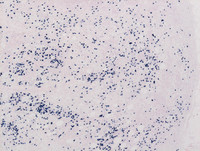

Figure 3: Breast lump-S-100

Nuclear and cytoplasmic S-100 protein expression is typical for these histiocytes (as opposed to reactive histiocytes which do not express S100). Also note the highlighted entrapped inflammatory cells in their cytoplasm, which are negative for S-100 protein (black arrow). Additionally, histiocytes in RDD are positive for CD68 and negative for CD1a expression, which helps differentiate this condition from other histocytic disorders like Langerhans cell histiocytosis and Erdheim-Chester disease.